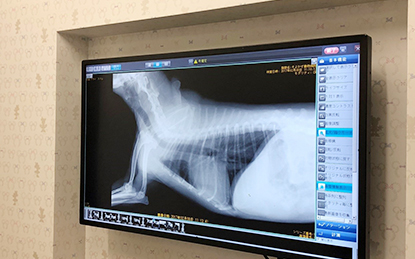

レントゲンモニター

わかりやすくご説明できる、大きくて見やすいレントゲンモニターを設置いたしました。

CRレントゲン装置(レジウス)

CRレントゲン装置を導入しております。

大きな画面で細部まで飼主様にご説明させていただきます。